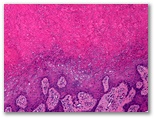

Granuloma piogenico

Diagnostico